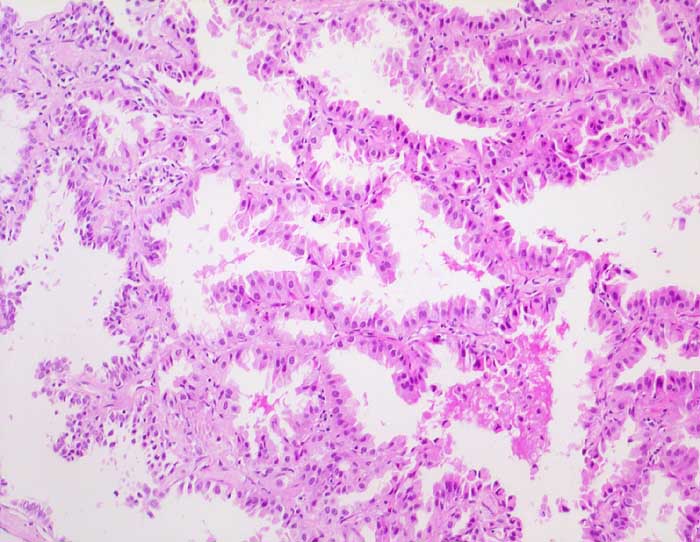

Bronchioloalveoläres Karzinom der Lunge

Das Bronchioloalveoläre Karzinom stellt eine Variante des Adenokarzinoms dar. Die Tumorzellen wachsen per Definition auf dem intakten Alveolargerüst, ohne das Stroma zu infiltrieren. Nicht selten zeigen Ausläufer gewöhnlicher Adenokarzinome ein bronchioloalveoläres Wachstumsmuster. Bei diesen Tumoren handelt es sich jedoch nicht um echte bronchioloalveoläre Karzinome. Da eine Invasion zytologisch nicht ausgeschlossen werden kann, ist die zytologische Diagnose eines bronchioloalveolären Karzinoms nicht eindeutig möglich. Die Karzinomzellen schilfern in kleinen Gruppen oder dreidimensionalen Verbänden in die Alveolarlichtungen ab. Multiple kleine papilliforme Zellverbände, die mit Creolakörperchen verwechselt werden können, sind typisch. Im Sputum erscheinen die Tumorzellen kleiner als die der üblichen Adenokarzinome. Die Kerne liegen exzentrisch, sind rund und glatt begrenzt, das Chromatin ist blass. Kernkerben und Pseudoinklusionen sind möglich, Nukleolen sind unauffällig. Das reichlich vorhandene Zytoplasma färbt sich blass eosinophil bis blass zyanophil. Beim muzinösen Subtyp ist es unterschiedlich vakuolisiert. Aufgrund der geringen Kernatypien ist die Unterscheidung von einer Becherzellhyperplasie bisweilen schwierig. Pseudoepitheliale Verbände aktivierter Makrophagen und hyperplastische Alveolarzellen, wie sie bei Lungeninfarkten oder Lungenfibrosen vorkommen verschwinden im Gegensatz zum ähnlich aussehenden bronchioloalveolären Karzinom in wiederholten Sputumkontrollen.

Der erste Fall zeigt ein muzinöses, der zweite Fall ein nicht muzinöses bronchioloalveoläres Karzinom.